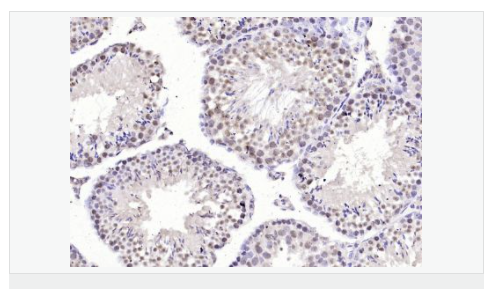

image.png